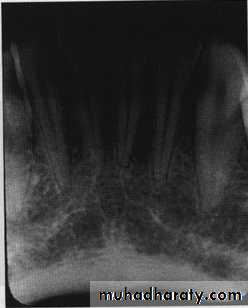

First visual circuit

Periapical before bitewing images

Right maxilla to left; left mandible to right.

*One anatomic structure at a time : eg . In posterior maxilla look at: maxillary sinus, maxillary tuberosity, zygomatic process

*Normal anatomy: eg.bones, canals, foramina.

*Check for symmetry.